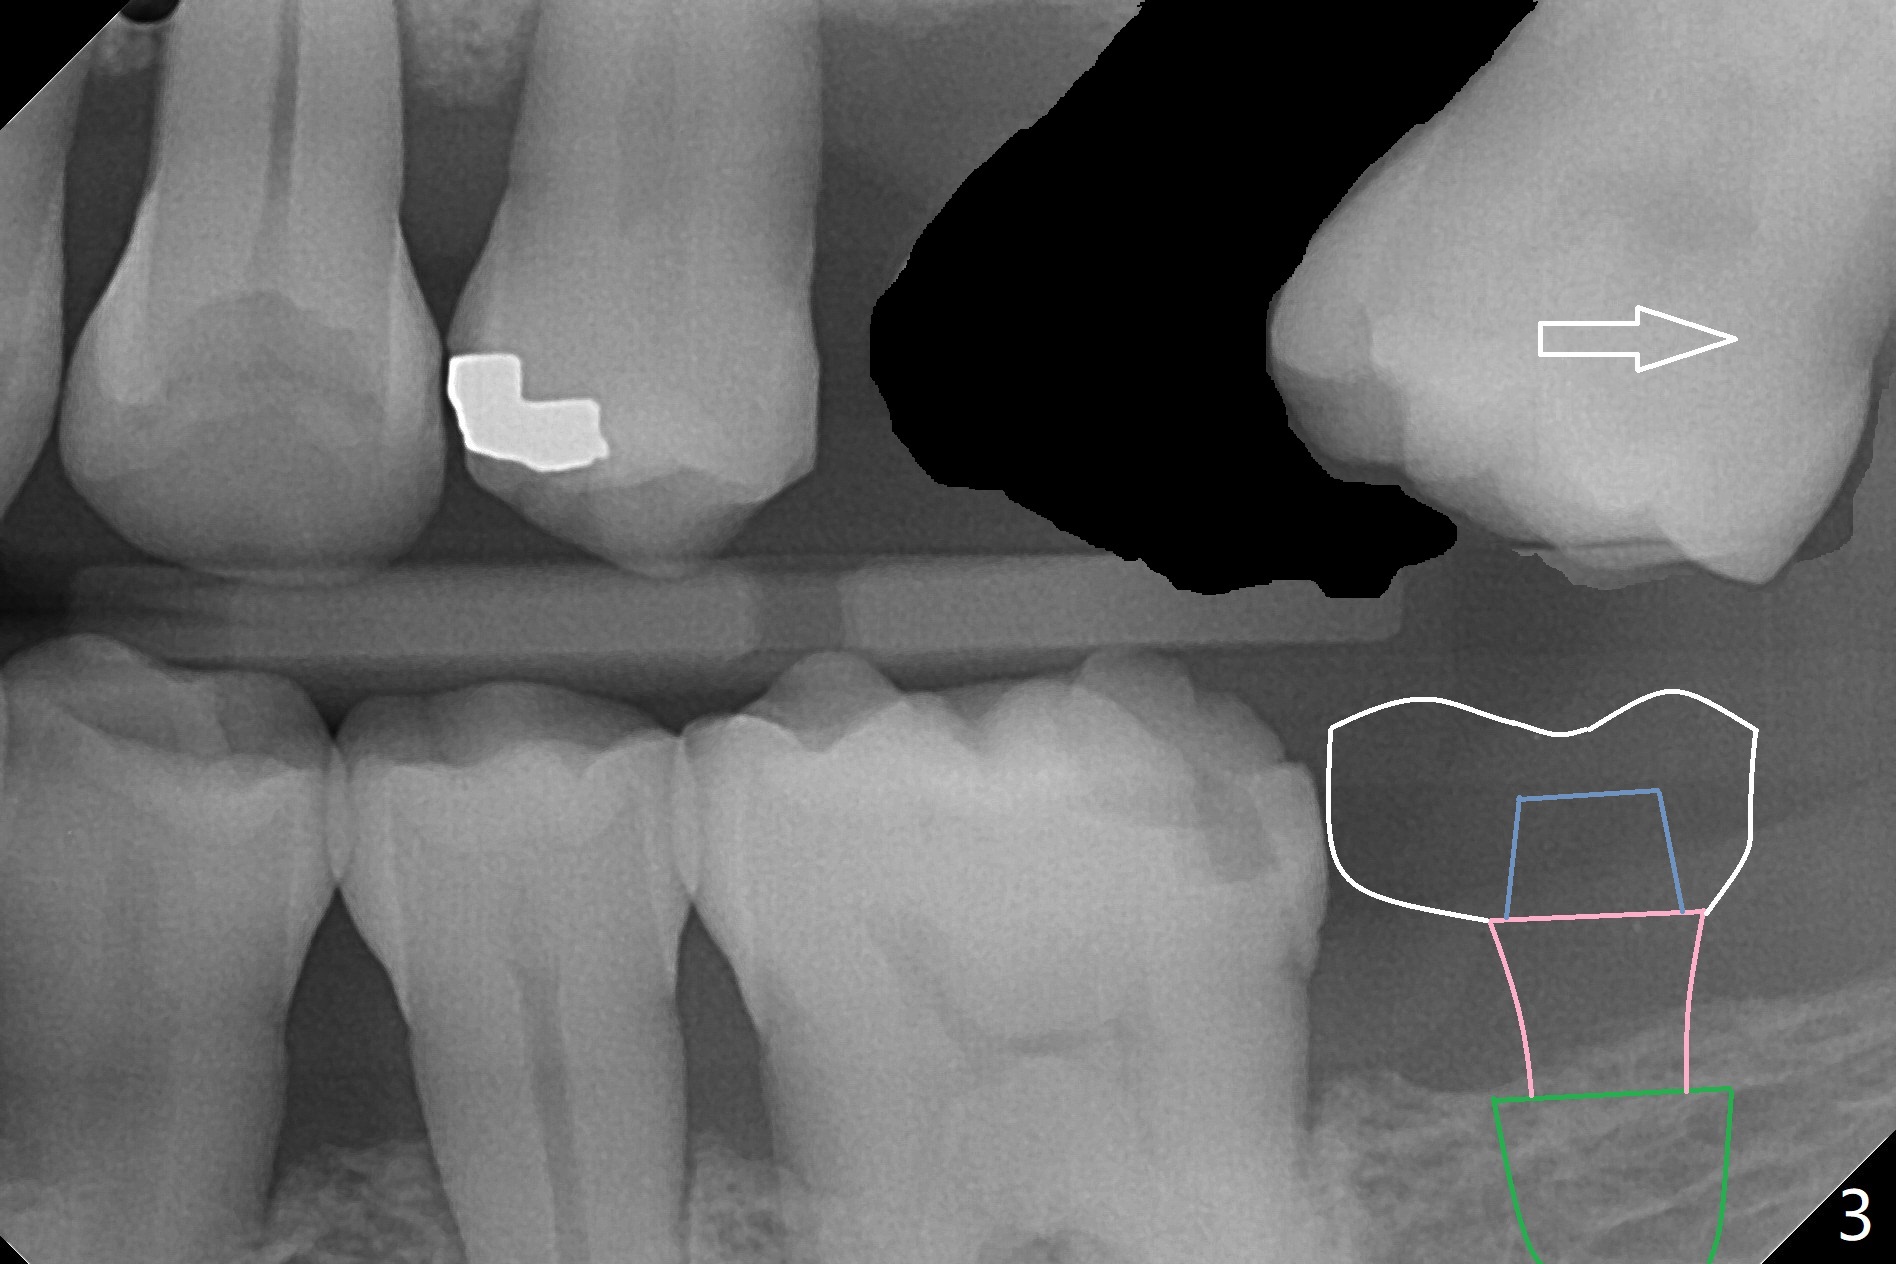

Crown/Implant Ratio

A 53-year-old man has signs of bruxism (Fig.1 diastema *) and root fracture or RCT failure at #4 (Fig.4 (large PARL *)). The RCT failure is related to overload of the affected tooth, which is in turn partially due to infraocclusion of the neighboring implant crown (Fig.1 arrows (implant positioning not ideal)) and partially to due to partial edentulism (Fig.2 missing teeth #14 and 18). For long term, limited ortho will be performed to upright and distalize the tooth #15 (Fig.3 arrow), followed by implants at #14 and 18. For now, the tooth #4 will be extracted (Fig.5), followed by osteotomy in the distal slope of the socket with guide (Fig.6 to get good trajectory). To place a bone-level implant (Fig.7 green), an abutment (blue) with long cuff (pink) is to be used. With poor implant/crown (white) ratio, stress occurs at the junction of the implant/abutment (red arrow), resulting in easy abutment screw loosening. In contrast, stress may be applied to directly to a tissue-level implant (Fig.8 arrow) with less likelihood of abutment screw loosening. The implant/crown ratio improves by approximately 5.5 mm. The roots of the teeth #15 and 16 are so close to each other that interference may occur when the tooth #15 is being uprighted (Fig.9). The empty socket of the tooth #4 is wide buccopalatal (Fig.10); the buccal plate is resorbed coronally (Fig.10 <) so that a 4.5 or 5 mm diameter implant should be placed palatal (Fig.11). Use sticky bone to repair the buccal plate defect and PRF membrane or plug for sinus lift. Following #15 uprighting and distalization, a 5x10 mm implant will be placed at #14; the ridge is triangular (Fig.12 <) so that bone trimmer is needed. A 10 mm long implant will be placed at #18 (Fig.14) to avoid perforating to the submandibular fossa (Fig.13 *).